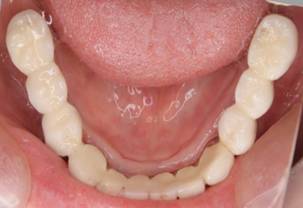

術後。上部構造はハイブリッドレジンです。しっかり嚙めるようになり喜んでいただきました。

下顎

上部構造装着後6年。ハイブリッドレジンを使用したため、少し艶がなくなってきました。上部構造の材料には金属、ハイブリッドレジン、セラミックなどがあります。セラミックはきれいですが欠けやすいため、最近はフルジルコニアを使っています。

下顎。12か月に一度メインテナンスをしています。